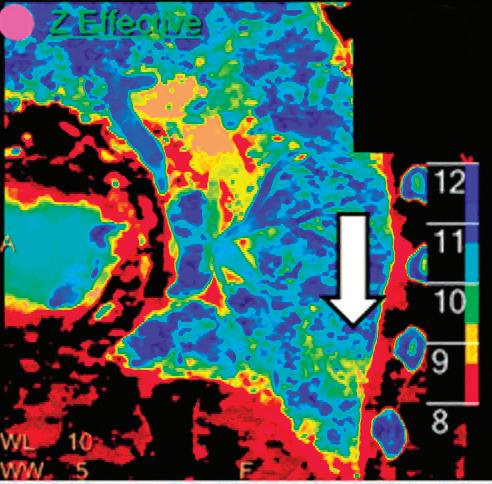

CT breath-hold results in a poor enhancement of the pulmonary arteries on the displays from left to right: monoenergetic 70 keV, monoenergetic 55 keV, monoenergetic 40 keV, and Z effective map showing a perfusion deficit of the lung parenchyma (white arrow). When decreasing the energy, the iodine attenuation is progressively boosted and reveals the presence of a thrombus (colored arrows) in a sub-segmental pulmonary artery corresponding to the territory of the perfusion deficit. (c) Monoenergetic 200 keV reduces beam hardening from dense contrast medium compared to conventional CT images.

Z Effective (Zeff)

Effective atomic number. Each voxel is set to a value in the range 5 to 30 representing the effective atomic number of that voxel. Z effective of air is set to zero. For reference, Z effective of water is 7.4, Z effective of cortical bone is 13.2, and Z effective of fat is 5.9. Z effective maps are very sensitive to materials characteristics (Figure 3) and can also be used to display perfusion maps and to identify very subtle perfusion deficits (Figure 2b). The accuracy measured on a Gammex phantom with iodine, calcium, and soft tissue inserts show that the majority of Z effective values are within 0.2 Z effective units and are consistent between 120 and 140 kVp scans.21